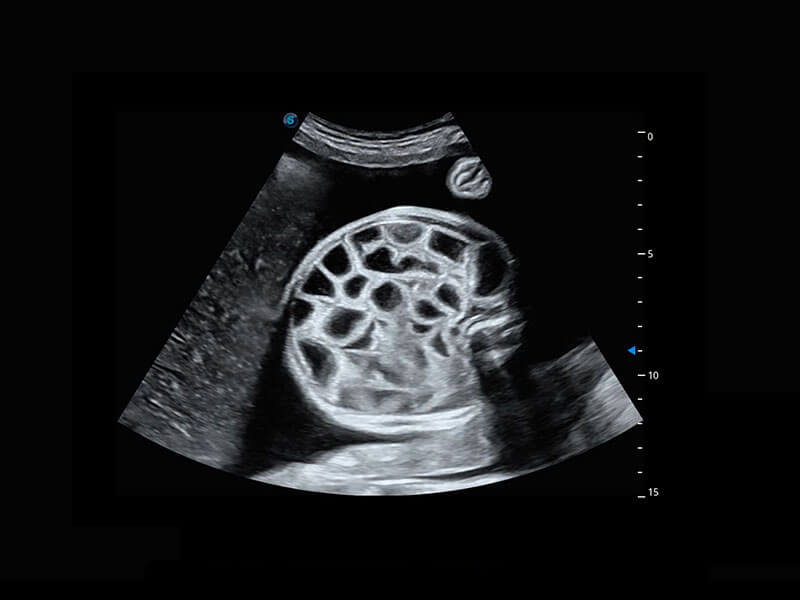

P60搭载一系列胎儿心脏成像技术,实现精细的胎儿心脏评估。

四腔切面